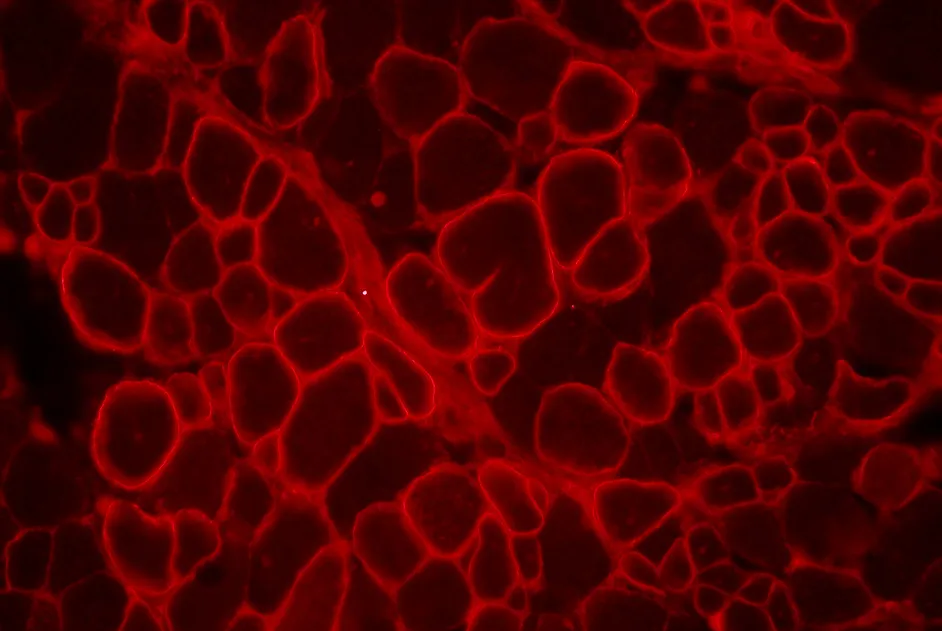

Des anticorps dirigés contre différentes parties de la dystrophine permettent de reconnaitre la dystrophine produites par des fibres révertantes.